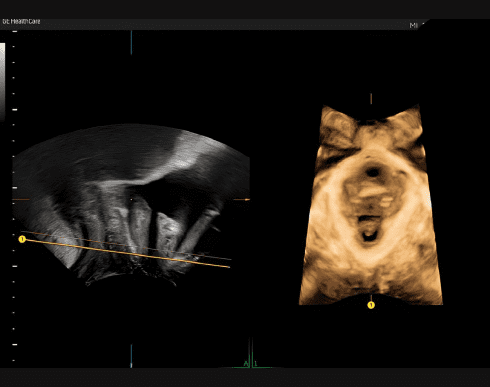

SonoPelvicFloor

Спрощує та пришвидшує оцінку тазового дна за допомогою автоматичного вирівнювання площини для отримання більш послідовних та відтворюваних результатів.

Зменшує час обстеження тазового дна до 75%.